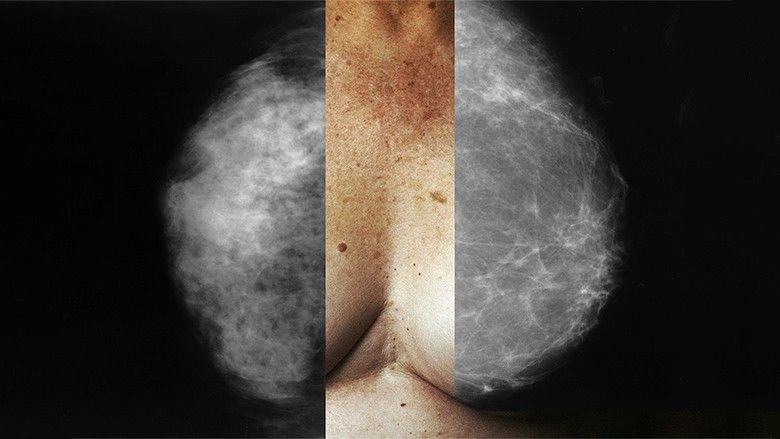

Kanceri i zorrës së trashë, është kanceri i tretë më i përhapur si tek femrat dhe tek meshkujt, Por, sipas një studimi të ri, ky lloj kanceri pritet të mos jetë më problem.